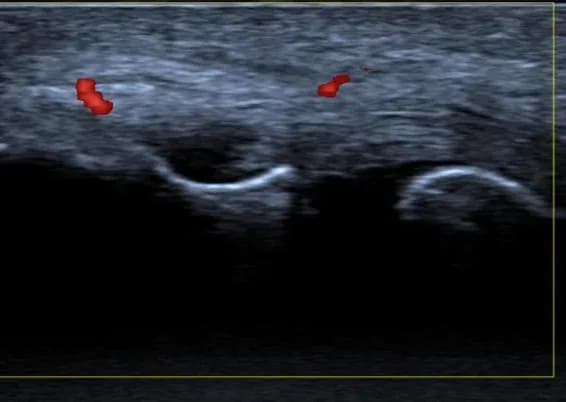

Tennisellenbogen

Die roten Flecken sind sogenannte Powerdopplersignale, welche in diesem Fall eine Neovaskularisation im Zuge einer ausgeprägten Tendinopathie anzeigen.